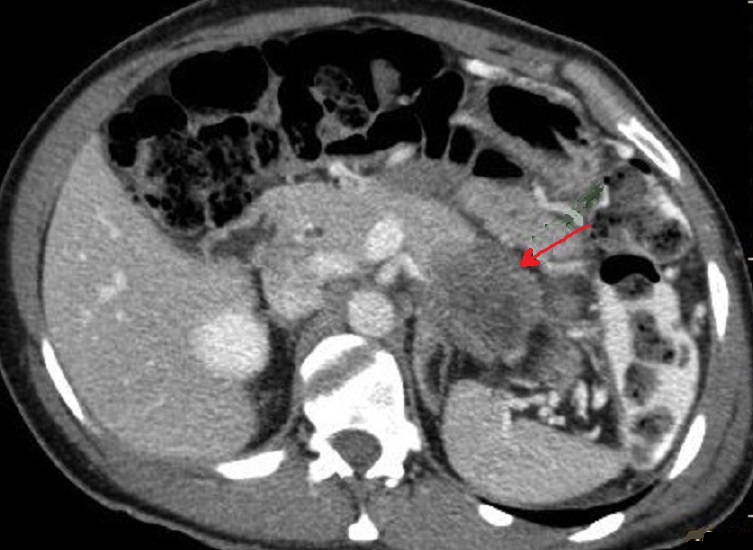

Effet de masse de la tumeur

se donne image de tumefie et deformation de contour

au queue du pancreas ( fleche rouge ) . Image

radiologique TDM d'une adenocarcinoma au queue du

pancreas ( coupe axiale ) |

Image de moins de

rehaussement de contrast intraveineuse est le

signe radiologique direct important pour diagnostic

la tumeur adenocarcinoma du pancreas (fleche rouge )

. Image radiologique TDM coupe axiale avec contrast

intraveineuse ( phase parenchymateuse ) |